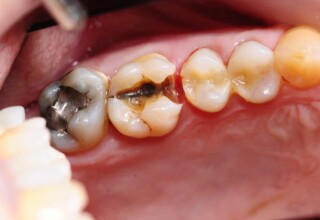

Αποκατάσταση Ραγισμένου Γομφίου με σφράγισμα Σύνθετης Ρητίνης

Τα ραγισμένα δόντια αποτελούν μια πρόκληση για την επανορθωτική οδοντιατρική από την άποψη της δυσκολίας της αποκατάστασης(συνήθως μεγάλα σφραγίσματα) άλλα κυρίως από τα προληπτικά μετρά που πρέπει να παρθούν για να αποφευχθεί ένα πλήρες κάταγμα. Η ακόλουθη περίπτωση παρουσιάζει την απλούστερη προσέγγιση της άμεσης συγκολλούμενης αποκατάστασης από σύνθετη ρητίνη. Βασίζεται στο σκεπτικό ενός συγκολούμμενου σφραγίσματος που «κρατάει» τα εναπομείναντα οδοντικά τμήματα «ενωμένα». Ο συγκεκριμένος γομφίος παρέμεινε ακέραιος για δυο χρονιά, οπότε χρειάστηκε απονεύρωση γιατί νεκρώθηκε και κατόπιν τοποθετήθηκε στεφάνη για αυξημένη προστασία.